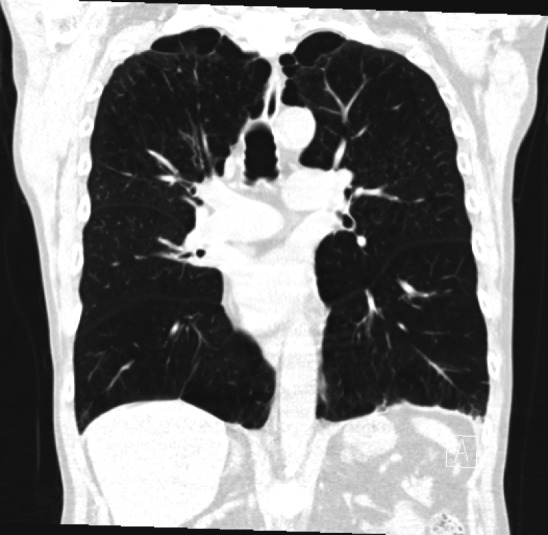

Point of Care Ultrasound (POCUS) is used to evaluate many clinical scenarios. Chest POCUS has been integrated as a part of a clinical protocol to assess patients with lung pathology 1. The ability to detect pneumothorax using chest POCUS has been shown to be superior to chest radiography, with specificity reported to be as high as 100% when a lung point sign is identified. In addition to improved diagnostic accuracy, chest POCUS has the added benefits of ease of access and absence of ionizing radiation. Here we describe a case where a patient with a high pre-test probability for pneumothorax had a detected lung point sign, but pneumothorax was ruled out via Computed Tomography (CT). This case highlights the importance of considering the mimics of the lung point sign. This case also shows a unique and interesting finding related to pleural movement restriction post-Bronchoscopic lung volume reduction (BLVR).